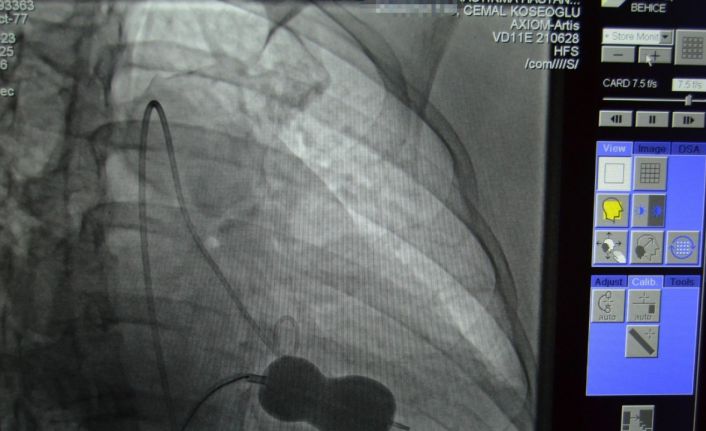

Antalya’nın Alanya ilçesinde Alanya Eğitim ve Araştırma Hastanesinde romatizmal mitral darlığı ve kalbin sağ tarafında büyüme tespit edilen Behice Kanmaz’a kardiyoloji hekimleri tarafından hastanede ilk kez uygulanan ameliyatsız işlemle kasığından girilerek mitral kapağı açıldı ve tedavi edildi.

Alanya’da yaşayan 45 yaşındaki hasta Behice Kanmaz, nefes darlığı ve çarpıntı şikâyetleri ile Alanya Eğitim ve Araştırma Hastanesi’ne başvurdu. Hastanede detaylı yapılan ön tetkik ve değerlendirmeler neticesinde Kanmaz’da romatizmal mitral darlığı ve kalbin sağ tarafında büyüme tespit edildi. Romatizmal kalp hastalığına bağlı mitral kapakta gelişen darlık ve mitral kapakta büyüme nedeniyle kardiyoloji hekimleri hasta Behice Kanmaz’ın mitral darlığının ameliyatsız tedavisine karar verdi.

Yapılan işlem ile ilgili açıklama yapan ALKÜ Tıp Fakültesi Öğretim Üyesi Doç. Dr. Cemal Köseoğlu, “Hastanemizde ilk kez uygulanan bu işlemi kardiyoloji birimi hekimleri olarak birlikte değerlendirdik ve mitral balon yardımıyla işlemi yapma kararı aldık. Hastamız Behice Hanımı, Anjıyo ünitemizde hiç uyutmadan mitral balon yardımıyla ile kasıktan girerek daralmış kapağını bir buçuk saat süren işlem sonunda açtık. Son kontrollerimizi yaptık. Hastanın kalp kapağı gayet güzel çalışıyor. 2 gün yoğun bakımda takibi sonunda taburcu işlemlerini gerçekleştireceğiz” ifadelerini kullandı. Doç. Dr. Köseoğlu; tıp teknolojisindeki gelişmeler ve giderek artan ameliyatsız müdahale imkanları ile çok ciddi kapak müdahalelerini çok düşük risklerle yapabilme olanağı bulduklarını da sözlerine ekledi.